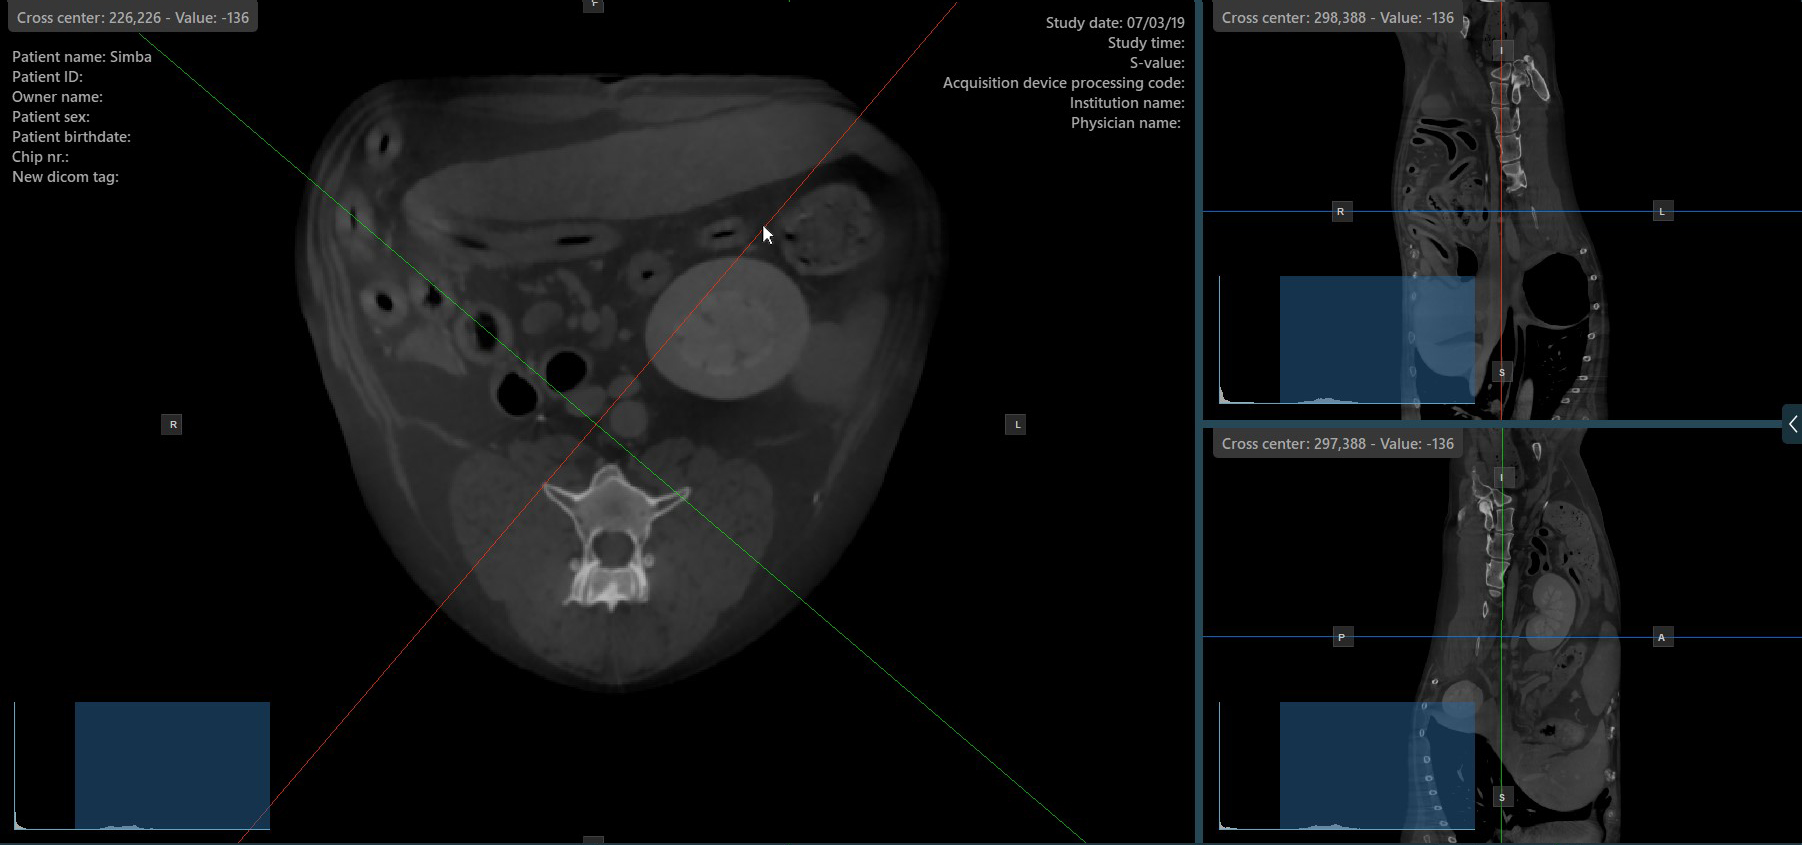

Press the Perpendicular Slicers icon in the left toolbar to activate simultaneous rotation of the slicers. Regardless of their previous orientation, the slicers are repositioned to be perpendicular to each other.

Toggle the Perpendicular Slicers option to switch the active mode of the slicers at any time, or choose one of the Tools -> Perpendicular Slicers or Tools -> Separate Slicers options from the CT Viewer menu.